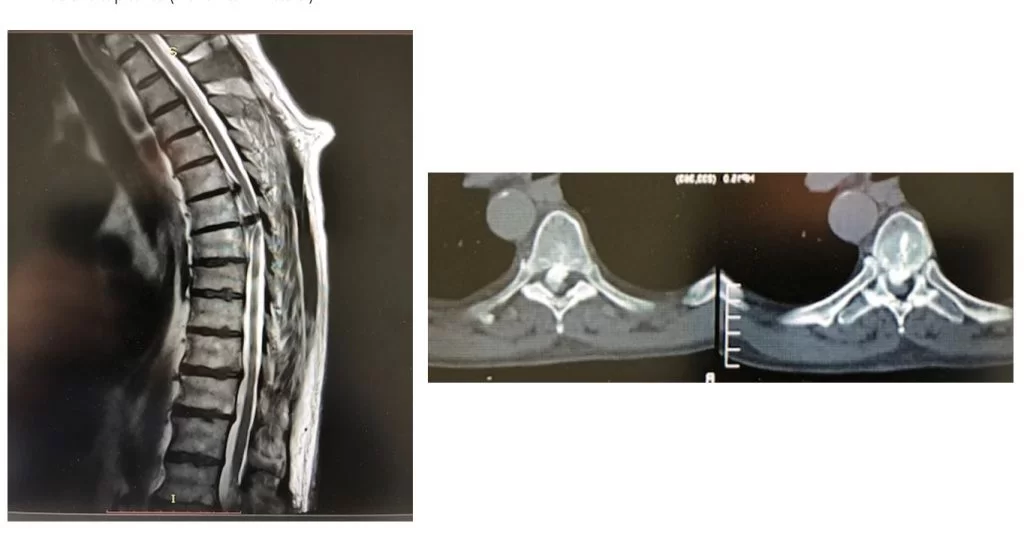

Διαθωρακικά: Δηλαδή με τη βοήθεια θωρακοτομής. Σ’ αυτή την περίπτωση η προσπέλαση γίνεται μέσα από τον θωρακικό κλωβό, δηλαδή ανάμεσα από τα πλευρά του θώρακα (Εικόνα 2 και 3).